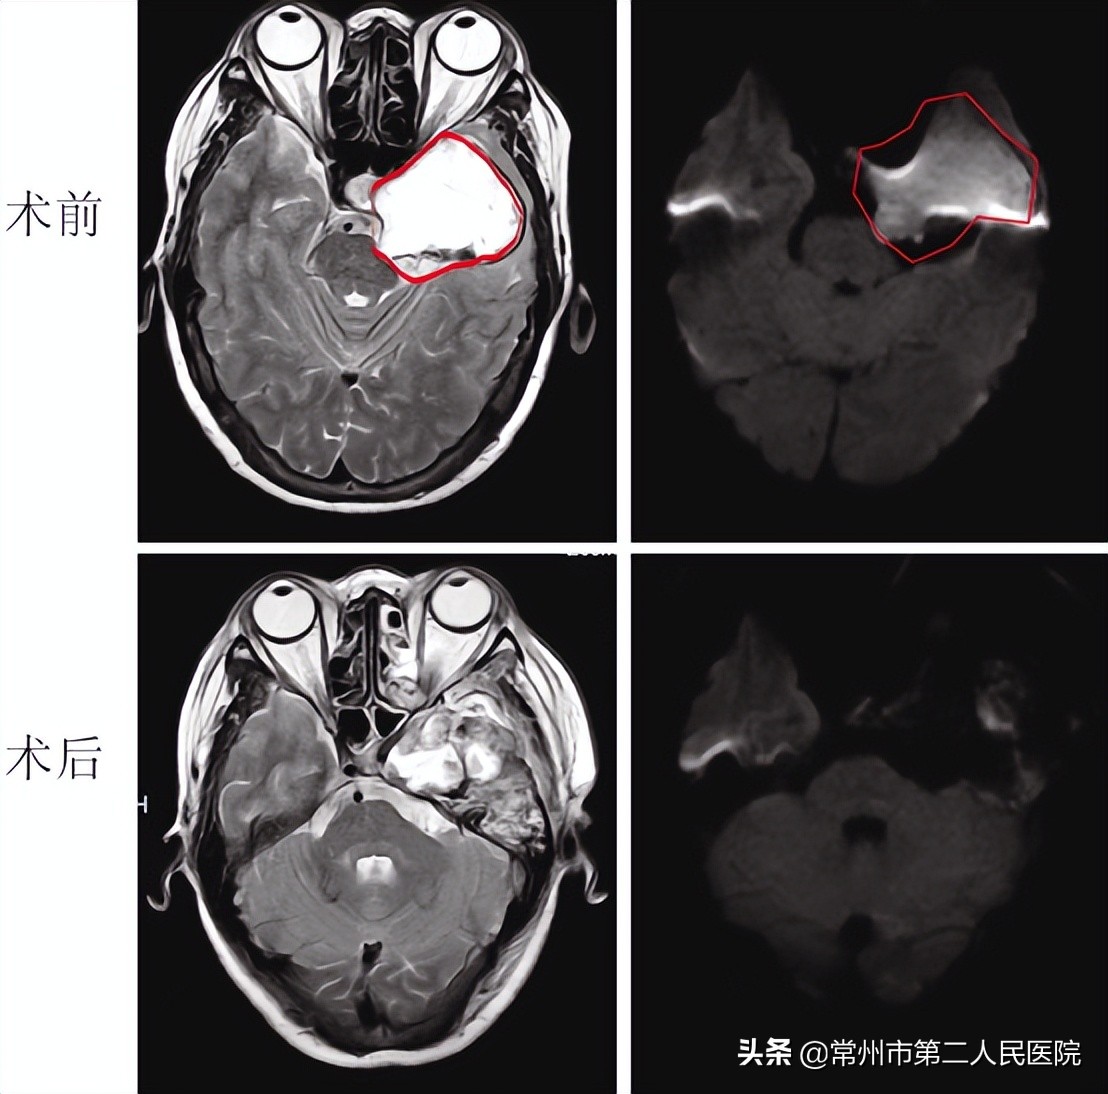

李阿姨曾多次到国内知名的大医院就诊过,但是被告知手术风险后,她选择了保守治疗。近期,李阿姨逐渐出现了左侧眼球活动障碍,还伴有面部麻木不适,再次复查头颅磁共振后,发现肿瘤已明显长大,直径约6cm,犹如鹅蛋大小,并且压迫到了最重要的结构——脑干。

经过几天详细的术前准备,李阿姨接受了开颅手术治疗。刘芳带领手术团队采用标准的颅底手术入路,并利用神经导航、电生理监测、超声吸引刀等手术设备,完全摘除了这个巨大的肿瘤,神经功能也得到了完整保留。手术历时5小时,李阿姨转危为安。

在神经外科护理团队的通力配合和精心照料下,李阿姨很快克服了术后并发症,术后磁共振显示肿瘤被完全切除,原有外展神经压迫的情况在后期会逐渐得到恢复。术后病理提示肿瘤是海绵窦区域较为少见的胆脂瘤。